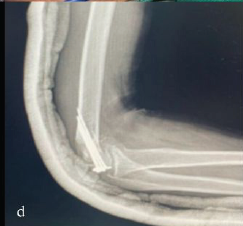

Medial Epicondyle Fractures Treated with Diverse Fixation Techniques: A Case Series

Santosh D Ghoti , Akshay D Punekar , Jaideep Das , Ajit Rathod , Harsh Jain , Rajath S Shetty

………………………………p.364-370